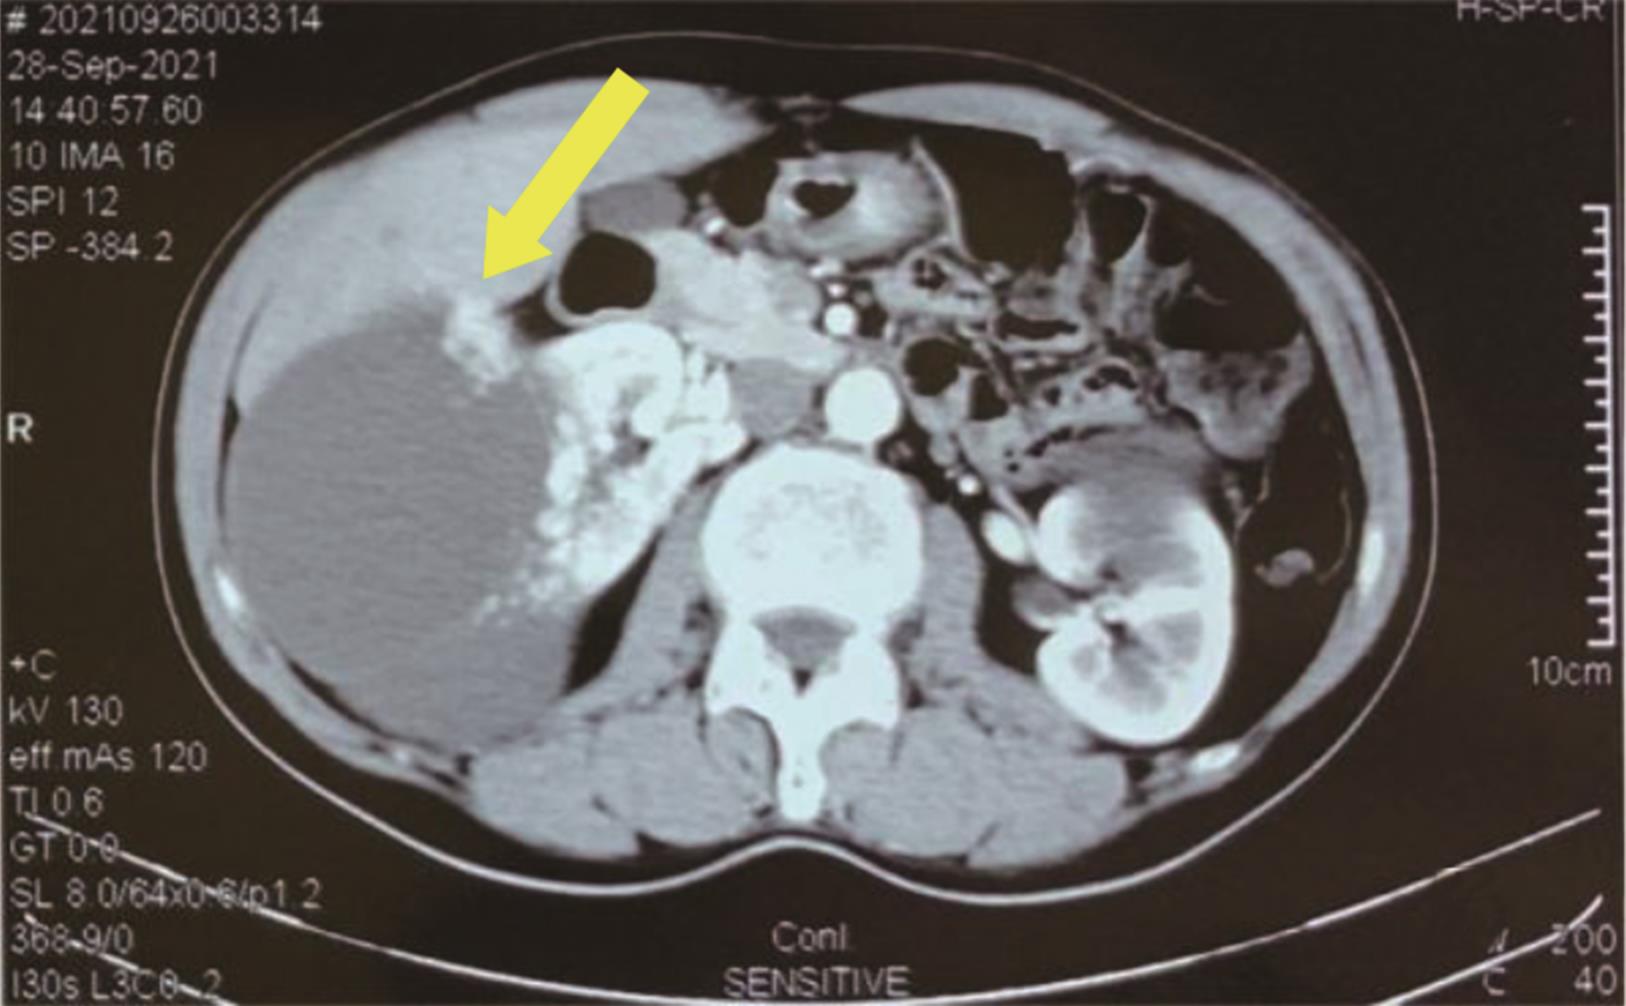

• 转移性上尿路上皮癌在维迪西妥单抗联合替雷利珠单抗新辅助治疗后行根治性肾盂癌切除术1例报道

2023, 48(8):1005-1008. DOI: 10.13406/j.cnki.cyxb.003299

摘要 (52) HTML (36) PDF 2.16 M (1929) 评论 (0) 收藏